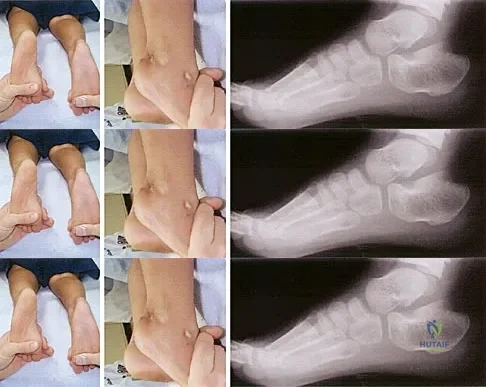

Question 73

Figure 14 shows the clinical photographs and radiograph of an 8-year-old girl who has a progressive equinus deformity of the right ankle. There is no history of trauma or infection. What is the most likely diagnosis?